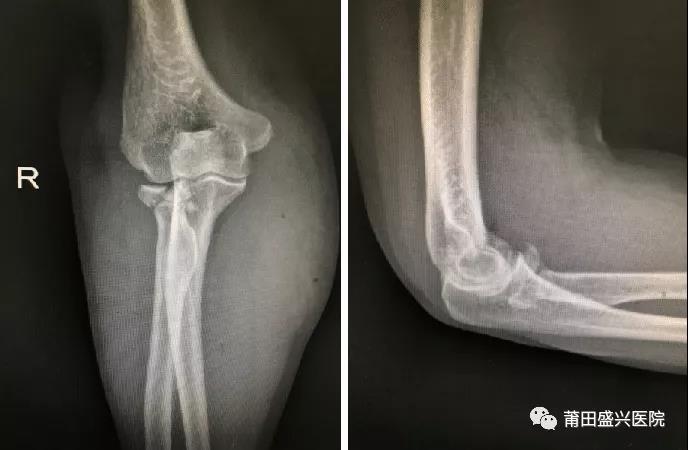

對于成人橈骨頭骨折Mason III型來說,橈骨頭就成為維持肘關(guān)節(jié)軸向和外翻穩(wěn)定的主要……